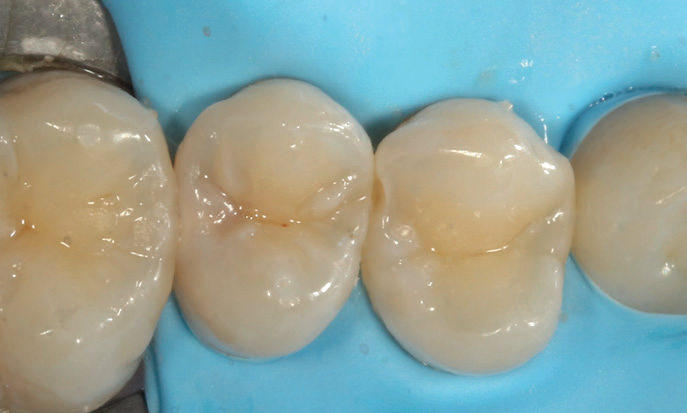

The patient was booked for the filling appointment, where I administered a local anaesthetic. As this was her first filling, the aim was to ensure a pleasant experience. I prefer working under a rubber dam for better control during the procedure, although Stela does not require one.

Figure 3: The teeth are isolated using a rubber dam